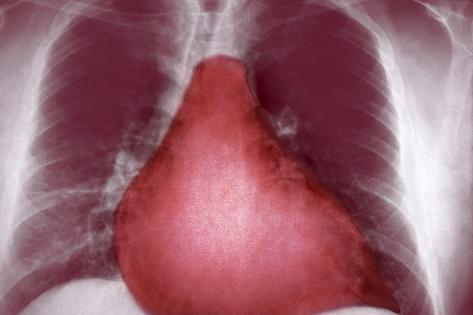

Learn how heart disease and heart failure is diagnosed in dogs and cats. (x-ray). A chest x-ray can show abnormalities in the size and shape of the heart and large blood vessels that may indicate heart disease. ... Read Article

Chest X-Ray Interpretation For The Internist

Chest X-ray Interpretation For Critical Care Transports